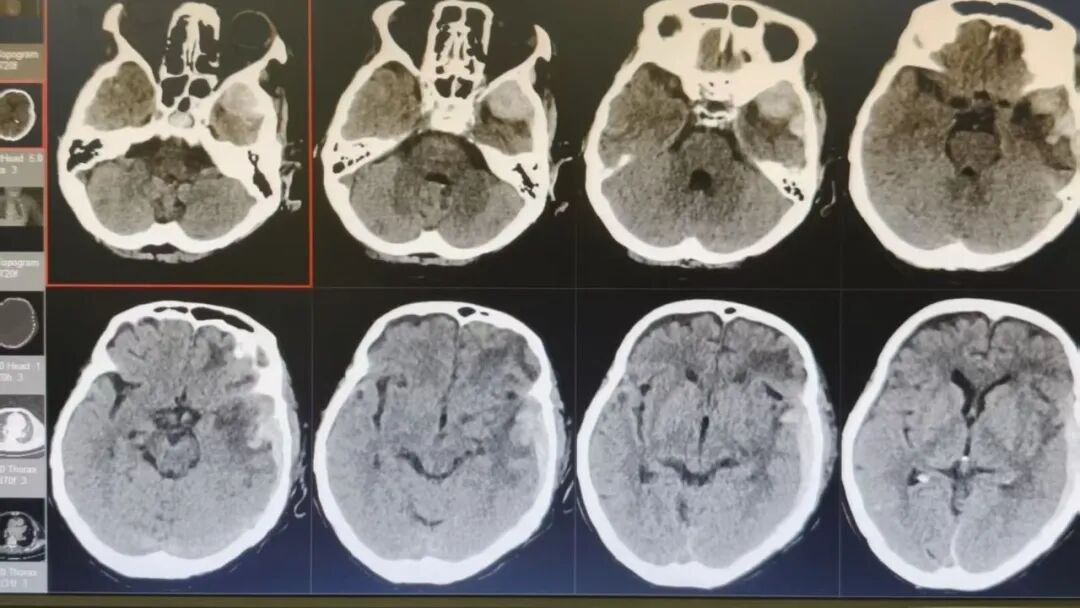

89岁的吴阿婆(化名)突发意外,被发现时已意识不清、陷入昏迷。家人发现后,紧急将其送往漳州第三医院,检查结果令人揪心:重型颅脑损伤、脑内大面积出血,加之O型Rh(D)阴性熊猫血、严重贫血……多重致命高危因素叠加,病情十分危重。

入院时

如此复杂凶险的状况,在常人看来几乎已是绝境!但漳州第三医院神经外科团队没有放弃,考虑到阿婆身体条件极差、血型特殊、手术风险难以预估,最终摒弃常规开颅方案,为她量身制定了个体化精准保守治疗方案,在绝境中为生命守住一线希望。